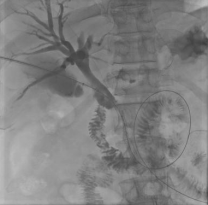

★针对恶性梗阻患者:通过此路径成功引流淤积的胆汁,有效降低黄疸、改善肝功能,为后续治疗赢得了宝贵时间,并可进一步植入支架,实现长期引流。

通过建立的通道,使用球囊取石 胆管癌植入支架